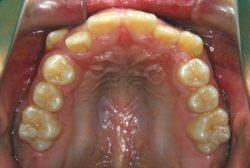

「歯並びの凸凹を直したい」という主訴で来院したケースです。診断の結果、たしかに「叢生」という隙間が足りないと言うことが原因の凸凹症例でした。

しかし、それ以上に問題なのは「前歯の噛み合い方が深すぎる」という症状で、初診の歯の正面写真を見ると下の前歯が全く見えません。こういう症状を矯正学では「過蓋咬合(かがいこうごう)」と言います。過蓋咬合を放置すると、将来的に顎関節に悪影響を与えるとされており、顎関節症の原因因子の一つです。また下の前歯の先端が、上の前歯の裏側の歯茎と強く接触するため、歯周病の原因にもなります。

検査の結果、凸凹が軽症なため非抜歯で矯正すること可能と判断、マルチブラケット装置にて治療しました。治療後は歯並びが綺麗になっただけでなく、噛み合わせ的にも正しい状態が確立しています。